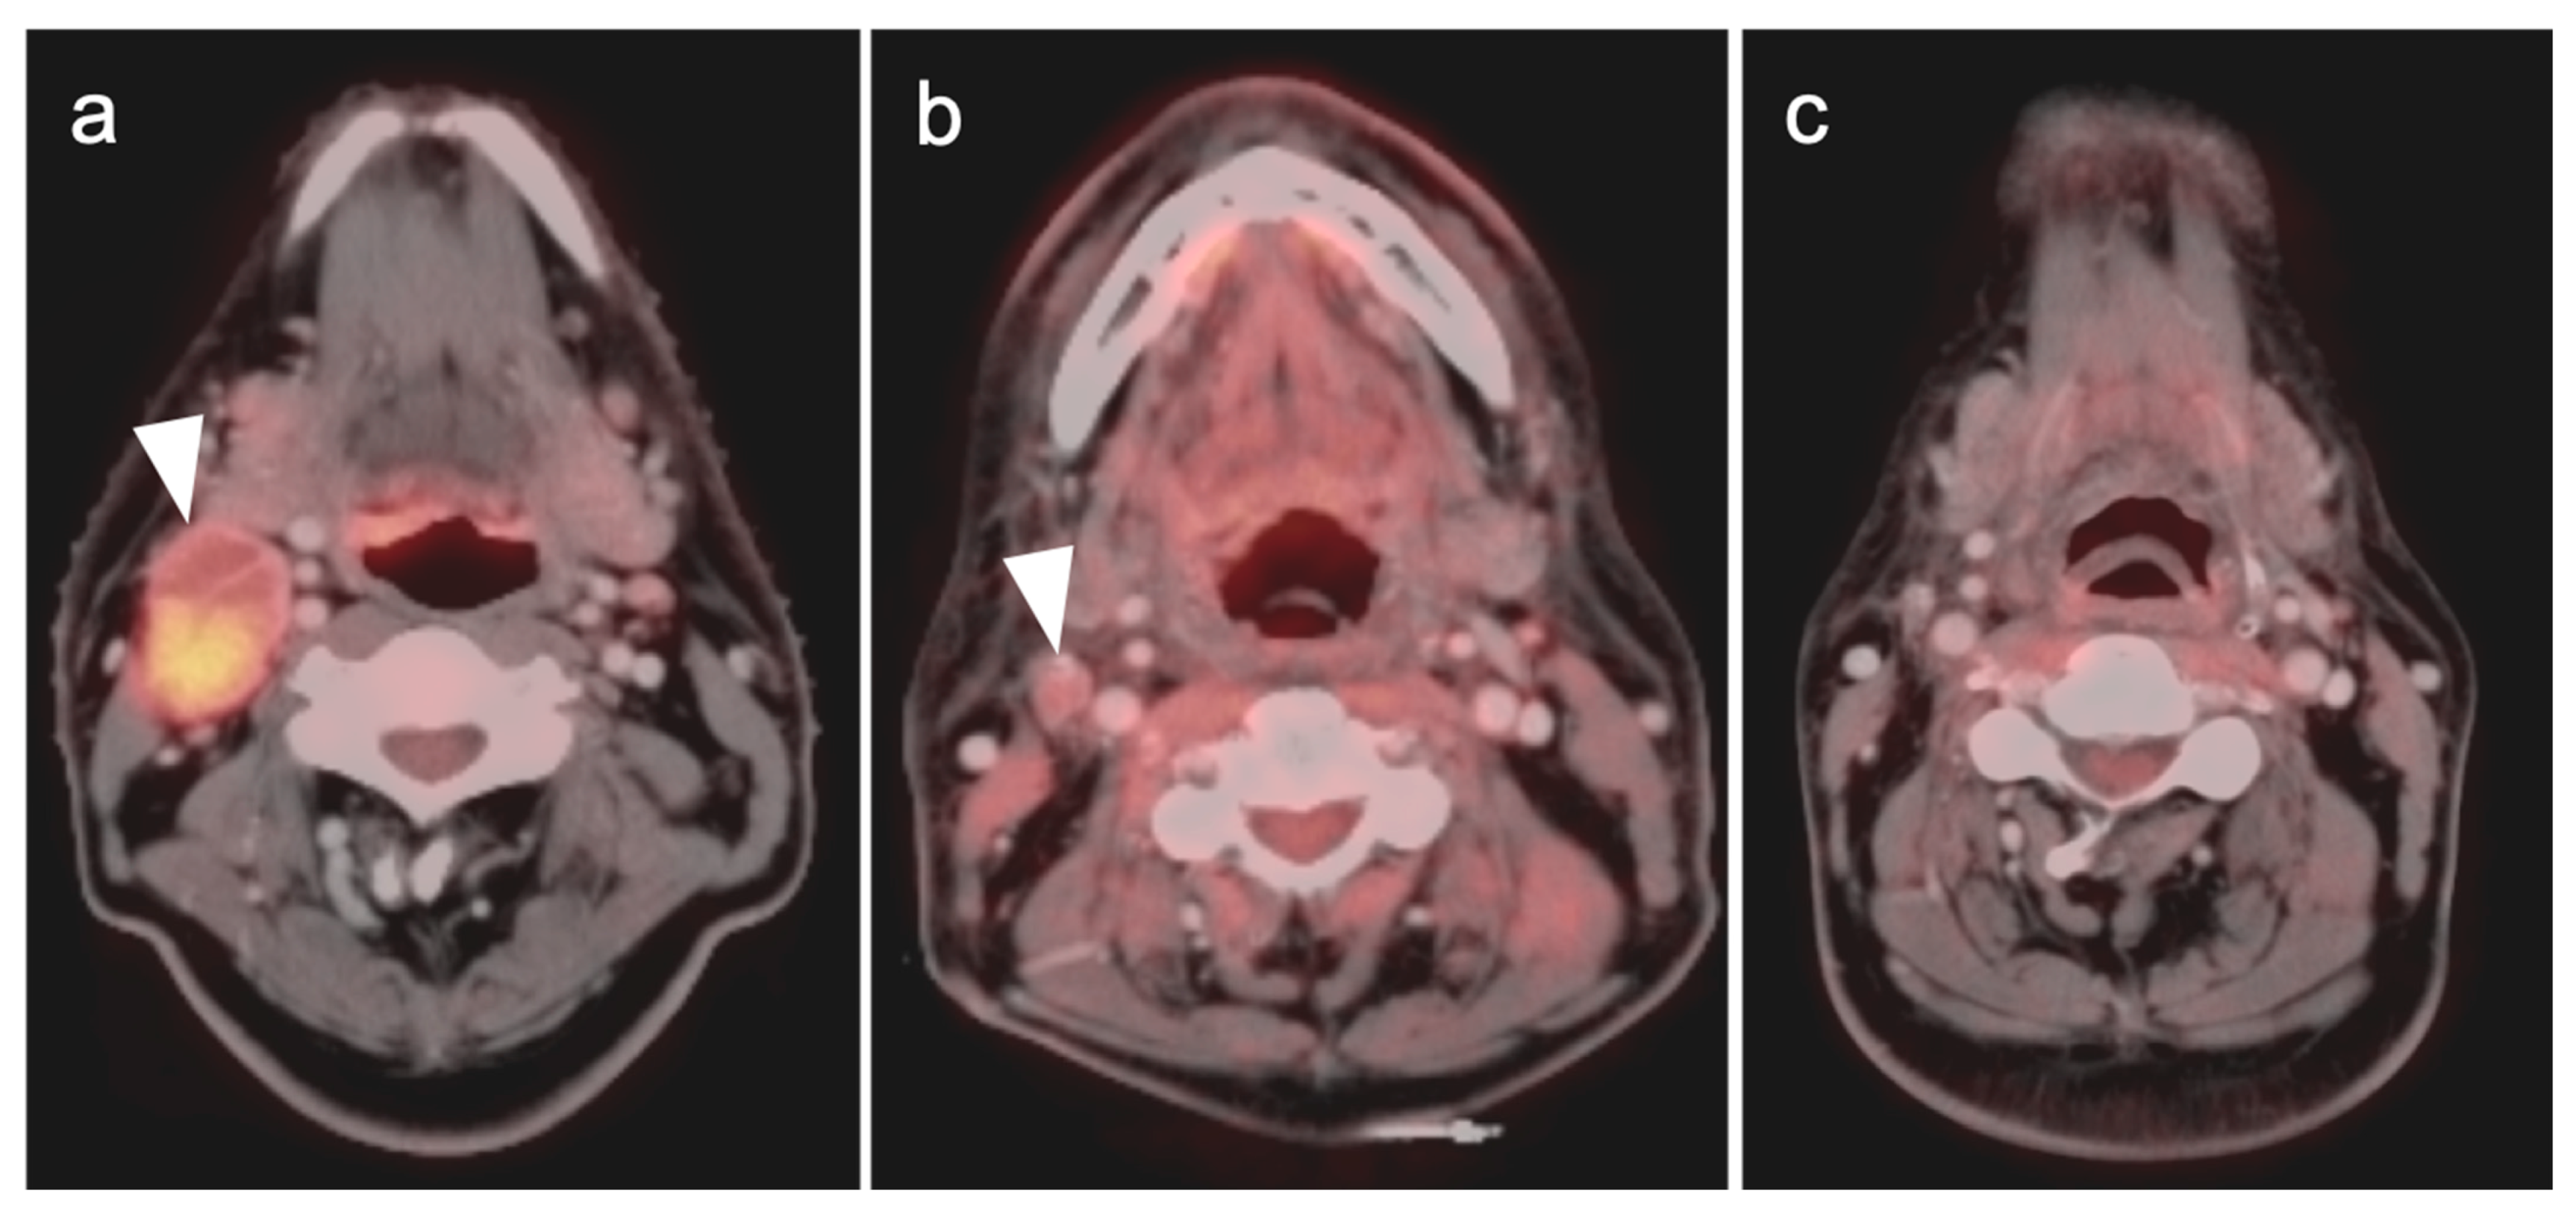

- Warthin tumor

- 3.